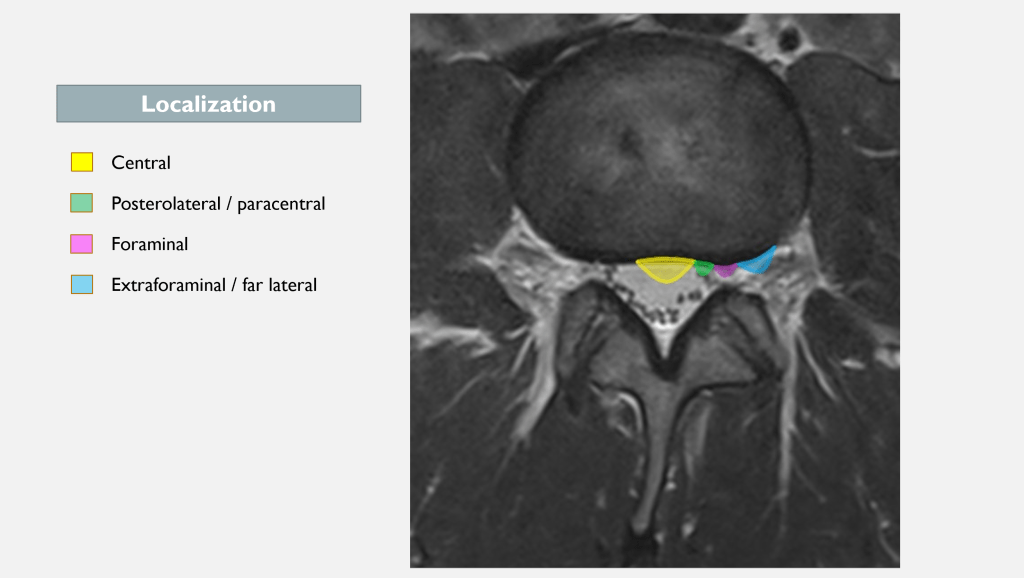

An easy way to classify disc herniations is: Central (medial), paracentral (posterolateral), and foraminal or extraforaminal (far lateral) (3).

Where the herniation is located is crucial for determining which structures it could potentially affect. For instance, a paracentral L4-5 disc herniation could impact the L5 nerve root, but if it’s positioned slightly more laterally, in the intervertebral foramen, it could affect the L4 nerve root (see image below).